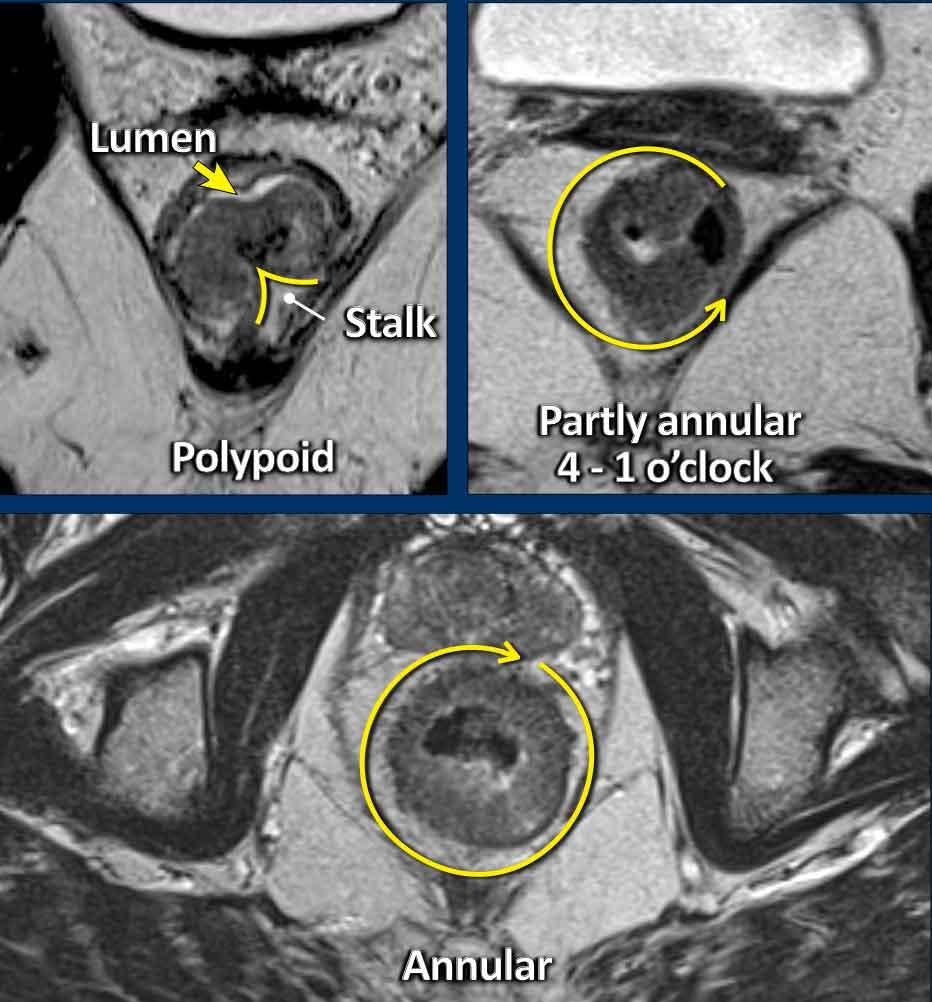

Khối u dạng polyp và dạng phẳng

Ung thư biểu mô tuyến trực tràng thường xuất phát từ các u tuyến, có thể là:

- Dạng polyp:Được nâng lên trên một cuống hoặc điểm bám khu trú, thường là độ thấp (T1–T2), nhô vào trong lòng ống.

- Không cuống:Phẳng, đáy rộng, thường biểu hiện dưới dạng dày thành hình vòng nhẫn một phần hoặc hoàn toàn.

Bờ xâm lấn:Vị trí bám của khối u vào thành trực tràng—bờ xâm lấn—là nơi khối u có thể xâm lấn ra ngoài thành trực tràng, do đó rất quan trọng trong việc phân loại giai đoạn T và đánh giá mức độ lan rộng ngoài thành.

Chu Vi Khối U:Mô tả mức độ bám thành trong báo cáo bằng cách sử dụng một trong hai:

- Ký hiệu mặt đồng hồ(ví dụ: “từ 3 đến 7 giờ”)

- Văn xuôi(ví dụ: “trước bên trái”).